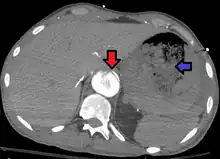

| Aorto enteric fistula and aortic dissection of the thoracic aorta. Arrow shows the flap in the aorta. Heterogeneity is blood in the stomach |

An aortoenteric fistula is a connection between the aorta and the intestines, stomach, or esophageus.[1] There can be significant blood loss into the intestines resulting in bloody stool and death.[1] It is usually secondary to an abdominal aortic aneurysm repair. The third or fourth portion of the duodenum is the most common site for aortoenteric fistulas, followed by the jejunum and ileum.

Diagnosis is typically via a CT angiography, esophagogastroduodenoscopy, or arteriography.[1] It is part of the differential diagnosis of gastrointestinal bleeding.[2]